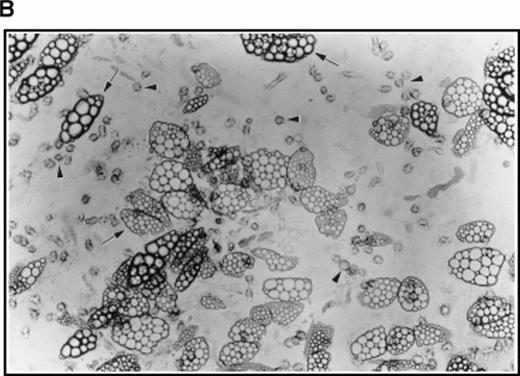

(A) Selection of quiescent bone marrow cells using 5-FU. Bone marrow mononuclear cells were incubated for 7 days in IMDM either supplemented with IL-3, SCF, and 5-FU to kill dividing cells (right-hand panels) or not (left-hand panels). At 4 days of incubation an aliquot was spun onto microscope slides and stained with Wright’s stain (top panels). Twenty-four hours before harvesting, 3H thymidine was added to the cultures. Following 7 days incubation cells were obtained and spun onto microscope slides. The slides were dipped in photographic emulsion and exposed for 7days before being developed, counterstained with Wright’s stain, and visualized under the light microscope (middle panels). (Bottom panels) Cells as above, but stained with antibody to c-kit and viewed under fluorescence. (B) Long-term culture. 5-FU–selected cells were plated on monolayers of bone marrow derived fibroblast as described in Materials and Methods and used to initiate long-term bone marrow cultures. The arrows show areas of extensive lipid deposition characteristic of these types of culture. Arrowheads identify “cobblestone areas,” clusters of developing hematopoietic cells.

Very few cells survived this procedure. Indeed, as assayed by Trypan blue staining of a small sample, all visible cells were found to be nonviable. However, when used to initiate long-term cultures on preformed, irradiated stroma, this population of cells proved very active in establishing hematopoiesis as evidenced by extensive lipid deposition and characteristic “cobblestone” areas (Fig 4B).